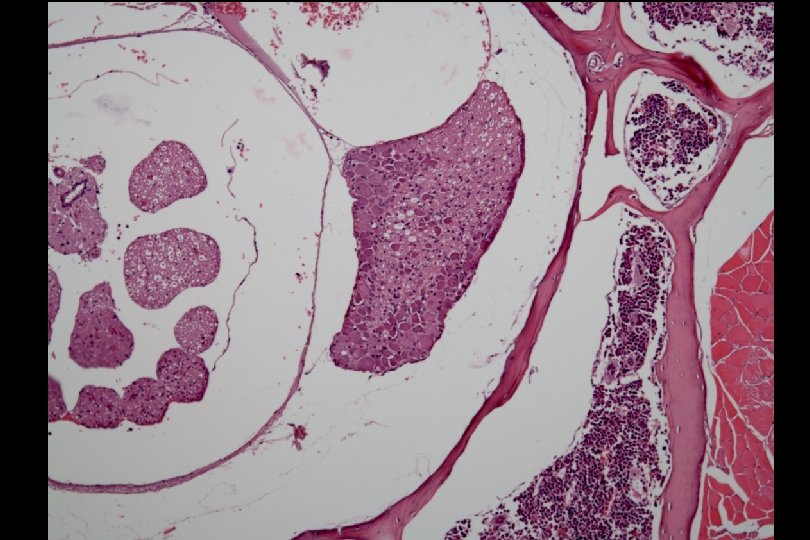

ENU-mutagenized mice displaying waddling behavior were linked to Chr. 18 151 M B 6, ♂ waddling (video) Normal BALB, ♀ BALB F 1 (video) Dominant Inheritance F 2 (video) Rough mapping Psy. Lab 2006 Dec

Four of five (80%) waddling mother mice did not nurse their pups The only one nursing mother killed all of her five pups at age 2 weeks.

Functional and Micro-Magnetic Resonance Imaging Center DWI_SE_BIO waddling control Lt Entorhinal cortex Lat ventricle TR=1500 ms TE=32 ms Slth=1 mm FOV=2 cm NEX=4 SW=41666. 6 Hz Big delta=15 ms Matrix =256*192 b=1100 s/mm 2

Functional and Micro-Magnetic Resonance Imaging Center DWI_SE_BIO waddling control Lat ventricle TR=1500 ms TE=32 ms Slth=1 mm FOV=2 cm NEX=4 SW=41666. 6 Hz Big delta=15 ms Matrix =256*192 b=1100 s/mm 2